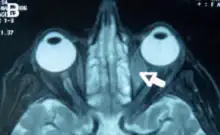

Orbital lymphoma is a common type of non-Hodgkin lymphoma that occurs near or on the eye. Common symptoms include decreased vision and uveitis. Orbital lymphoma can be diagnosed via a biopsy of the eye and is usually treated with radiotherapy or in combination with chemotherapy.